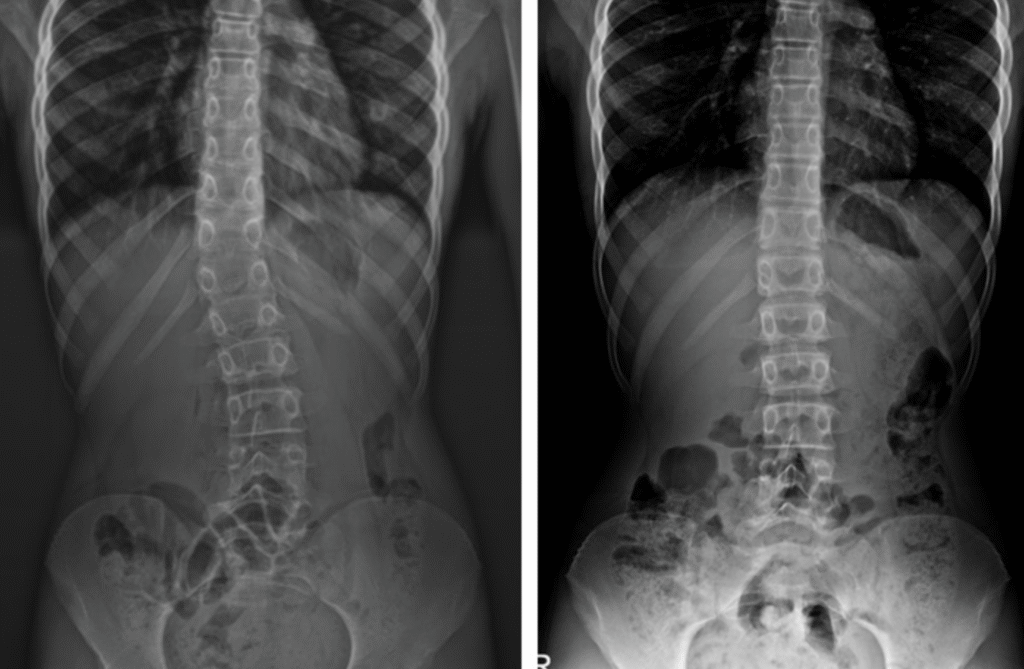

Dawid – 7 lat

Skolioza jednołukowa (statyczna) – zdj. z lewej. Korekcja uzyskana w trakcie jednej wizyty – zdj. z prawej